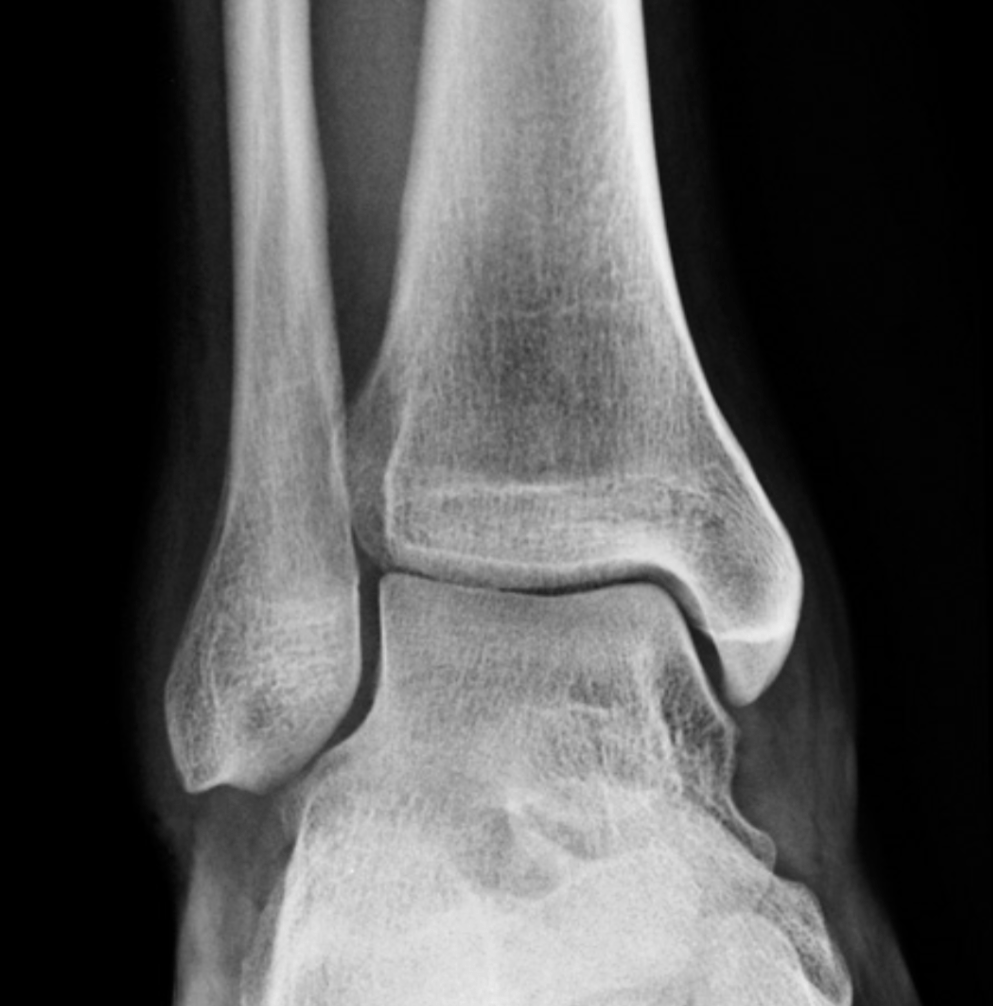

Name any abnormalities in the below imaging of ankle mortise

What is Normal?